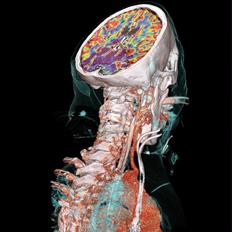

August 27, 2012 — A recent multi-center study, led by researchers from Wake Forest School of Medicine and published in the Journal of the American Medical Association (JAMA) has indicated that computed tomography (CT) scanning of the heart and measuring the coronary artery calcium (CAC) score is the most accurate predictor of cardiovascular disease for individuals at intermediate risk for heart disease.

August 22, 2012 — In a head-to-head contest between the New Orleans Criteria (NOC) and the Canadian Computed Tomography (CT) Head Rules (CCHR), the Canadian rules showed higher sensitivity and specificity in predicting neurosurgical intervention for mild head injury. The results of the study, conducted in Tunisia, were published online August 21, in Annals of Emergency Medicine ("Prediction Value of the Canadian CT Head Rule and the New Orleans Criteria for Positive Head CT Scan and Acute Neurosurgical Procedures in Minor Head Trauma: A Multicenter External Validation Study").

August 24, 2012 — On August 20, 2012, InSightec announced it received approval from the U.S. Food and Drug Administration (FDA) to begin Phase I clinical trials evaluating the use of its ExAblate Neuro system for the treatment of patients with tremor-dominant Parkinson’s Disease (PD). This device is the first clinical system to use magnetic resonance- (MR) guided focused ultrasound (MRgFUS) through an intact skull, offering noninvasive transcranial treatment without any incisions or ionizing radiation.